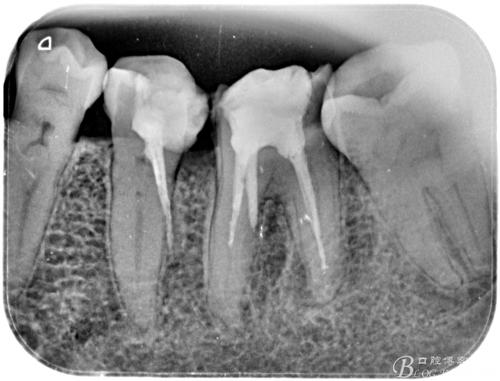

牙齿侧穿图片,根管侧穿图片

底穿 加侧穿

弯曲冠部的内侧牙本质和弯曲根尖部的外侧牙本质(如上图),造成侧穿